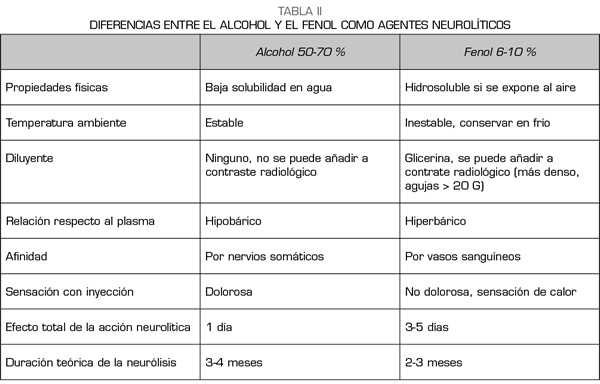

¿NEURÓLISIS CON ALCOHOL O CON FENOL?

El alcohol y el fenol son los dos agentes que se utilizan para la neurólisis química de la cadena simpática (63). El alcohol etílico es una solución incolora e hipobárica respecto al plasma, diluyéndose al 50-70 % para obtener un efecto simpaticolítico. El fenol no se comercializa en España y debe ser preparado previamente en la farmacia del hospital. Es inestable a temperatura ambiente y su vida media es de 1 año cuando se conserva en frío y lejos de la luz. Se suele utilizar a concentraciones de 6-10 % para los bloqueos simpáticos, ya que por debajo de 2 % solo produce un efecto anestésico y por encima del 20 % puede destruir nervios somáticos. Las propiedades químicas y diferencias entre ambos agentes pueden verse resumidas en la Tabla II.

Los trabajos que comparan el alcohol con el fenol en los bloqueos simpáticos son escasos. Koyyalagunta y cols. (63) publicaron un estudio retrospectivo de 93 pacientes con cáncer abdominal sometidos a neurólisis química de los nervios esplácnicos, valorando la eficacia, duración del bloqueo y efectos adversos de los dos agentes. No encontraron diferencias en el alivio del dolor ni en la incidencia de complicaciones. La infiltración tumoral del tronco celiaco y la radioterapia previa no interfirió en la eficacia del procedimiento, razón por la que los investigadores eligieron los nervios esplácnicos como diana.

Hay mucha variedad bibliográfica sobre qué tipo de agente usar y qué cantidad de volumen administrar, dependiendo básicamente de la diana elegida, el abordaje percutáneo, y la técnica de imagen que utilicemos. Para los bloqueos realizados por vía transcrural, se recomiendan unos 15-20 ml de agente neurolítico por cada lado, prefiriéndose el alcohol por su menor afinidad por los vasos sanguíneos. Para el abordaje ecográfico abdominal, son suficientes 8-10 ml de alcohol. Para la neurólisis de los nervios esplácnicos, se recomiendan 6-8 ml de fenol, por su menor afinidad por los nervios somáticos. Si utilizamos la técnica ecoendoscópica, el volumen también es bajo. LeBlanc y cols. (64) no encontraron diferencias entre la administración ecoendoscópica de 20 ml frente a 10 ml de alcohol.